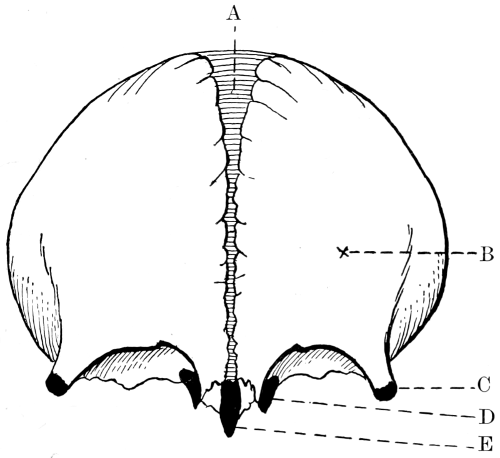

Fig. 2. Cranio-cerebral Topography. 1, 1, Reid’s base-line; 2, 2, A line parallel to the above at the level of the supra-orbital margin; 3, The middle meningeal artery; 4, The anterior branch; 5, 5, 5, The three sites for trephining; 6, The posterior branch; 7, The site for trephining; 8, The point for trephining to reach the descending horn of the lateral ventricle; 9, The lateral sinus; 10, The inion; 11, The mastoid process; 12, Macewen’s suprameatal triangle; 12a, The mastoid antrum; 12b, The facial nerve; 13, The suprameatal and supramastoid crests; 14, 14, The temporal crest; 15, The temporal fossa; 16, The external angular frontal process; 17, The tendo-oculi attachment; 18, The lachrymal groove. (Reproduced, by the permission of Mr. H. K. Lewis, from the author’s work on ‘Landmarks and Surface-markings’.)